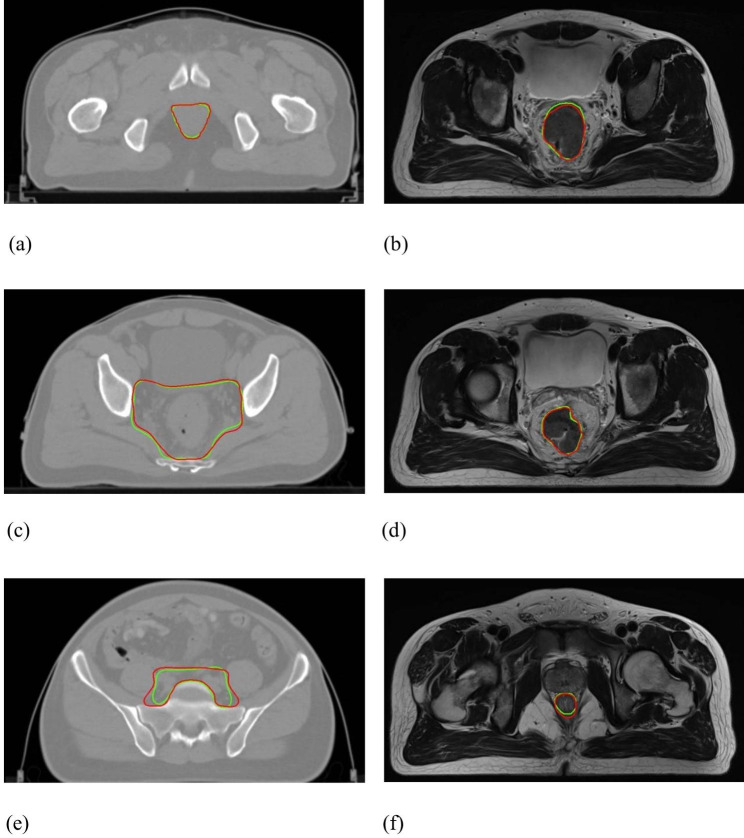

Representative axial illustration of Patient D: (a)&(c)&(e) CTV contours, where DSC = 0.88 and 95HD = 5.25 mm; (b)&(d)&(f) GTV contours, where DSC = 0.90 and 95HD = 5.22 mm. (GT-red line vs. DL-green line)

Fig. 4.

Figure 3 shows the DSC and 95HD value distribution over the testing patient cohort, and Fig. 4 shows the CTV and GTV contours of a representative patient case (Patient D). For DL-based CTV segmentation (green squares in Fig. 3&), the DSC values range from 0.69 to 0.97 with mean ± SD as 0.85 ± 0.06, and the 95HD values range from 1.37 to 32.71 with mean ± SD as 7.75 ± 6.42. Two outlier data points in Fig. 3(b) are easily identified, i.e., Patient K with 95HD = 32.71 mm, and Patient B with 95HD = 15.50 mm. Representative axial images of Patient K are shown in Fig. 5(a)&(c)&(e), where the CTV-GT contour indicates this is a special case. The medical record shows that this patient was with perirectal lymph node invasion (LNI), and therefore mesorectal, sacral, internal iliac regions should be covered. This special treatment inevitable induced relatively large distance errors. This goes similarly with Patient B that required additional coverage of lymph nodes. When these two outliers are removed, the 95HD values range from 1.37 to 8.1 (5.93 ± 1.55).